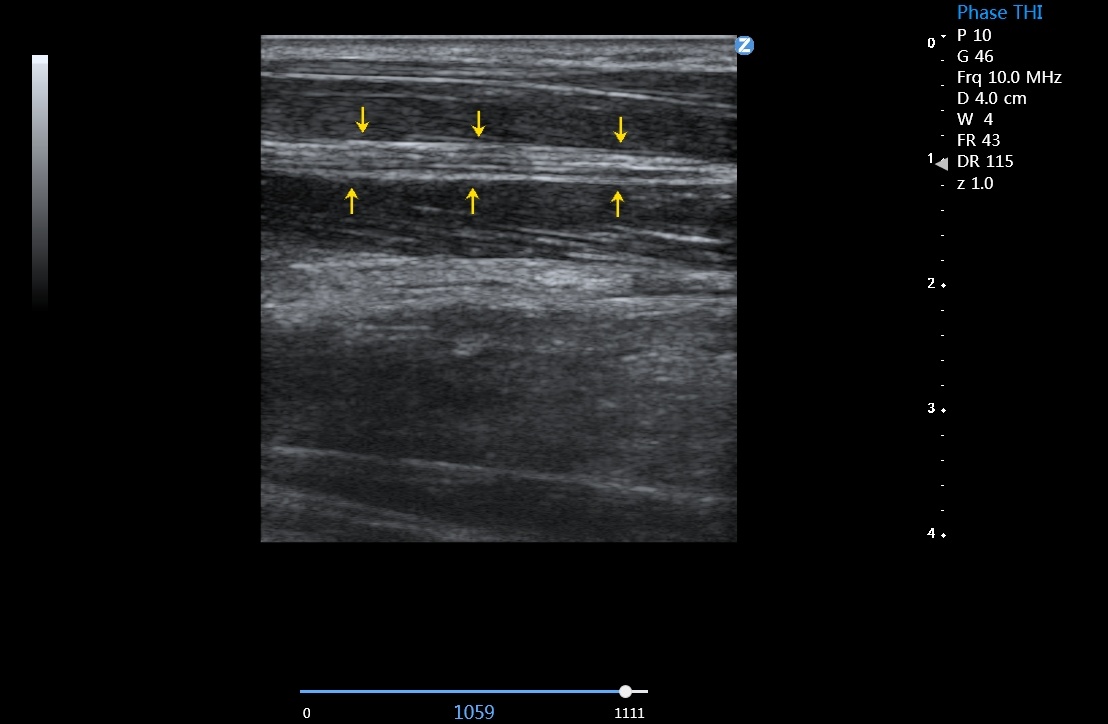

血管内中膜厚度自动测量 IMT

可以自动识别并自动测量血管内中膜的厚度,提供内中膜厚度测量报告,为心脑血管事件的预防提供评估指标